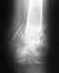

27 сентября 2009года сломал пятку,упав с высоты 3-4 метра.В скорой наложили лангетку сперед,через 5 дней в поликлинике,лангету сняли.Упаковали в гипс всю ногу на 2,5 месяца.Долго расхаживался.Более -менее хожу.На прошлой неделе сделал рентген на пленке,сказали артроз таранной кости(сзади отросток к пятке-артрозный).Мази,уколы,электрофарез,компрессы.Все это здорово,но убирает симптомы.Вопрос-вылечить совсем можно?Кроме бубнов и ольховых шишек...34 года,Дрорданом стать не мечтаю,но хочется быть здоровым.